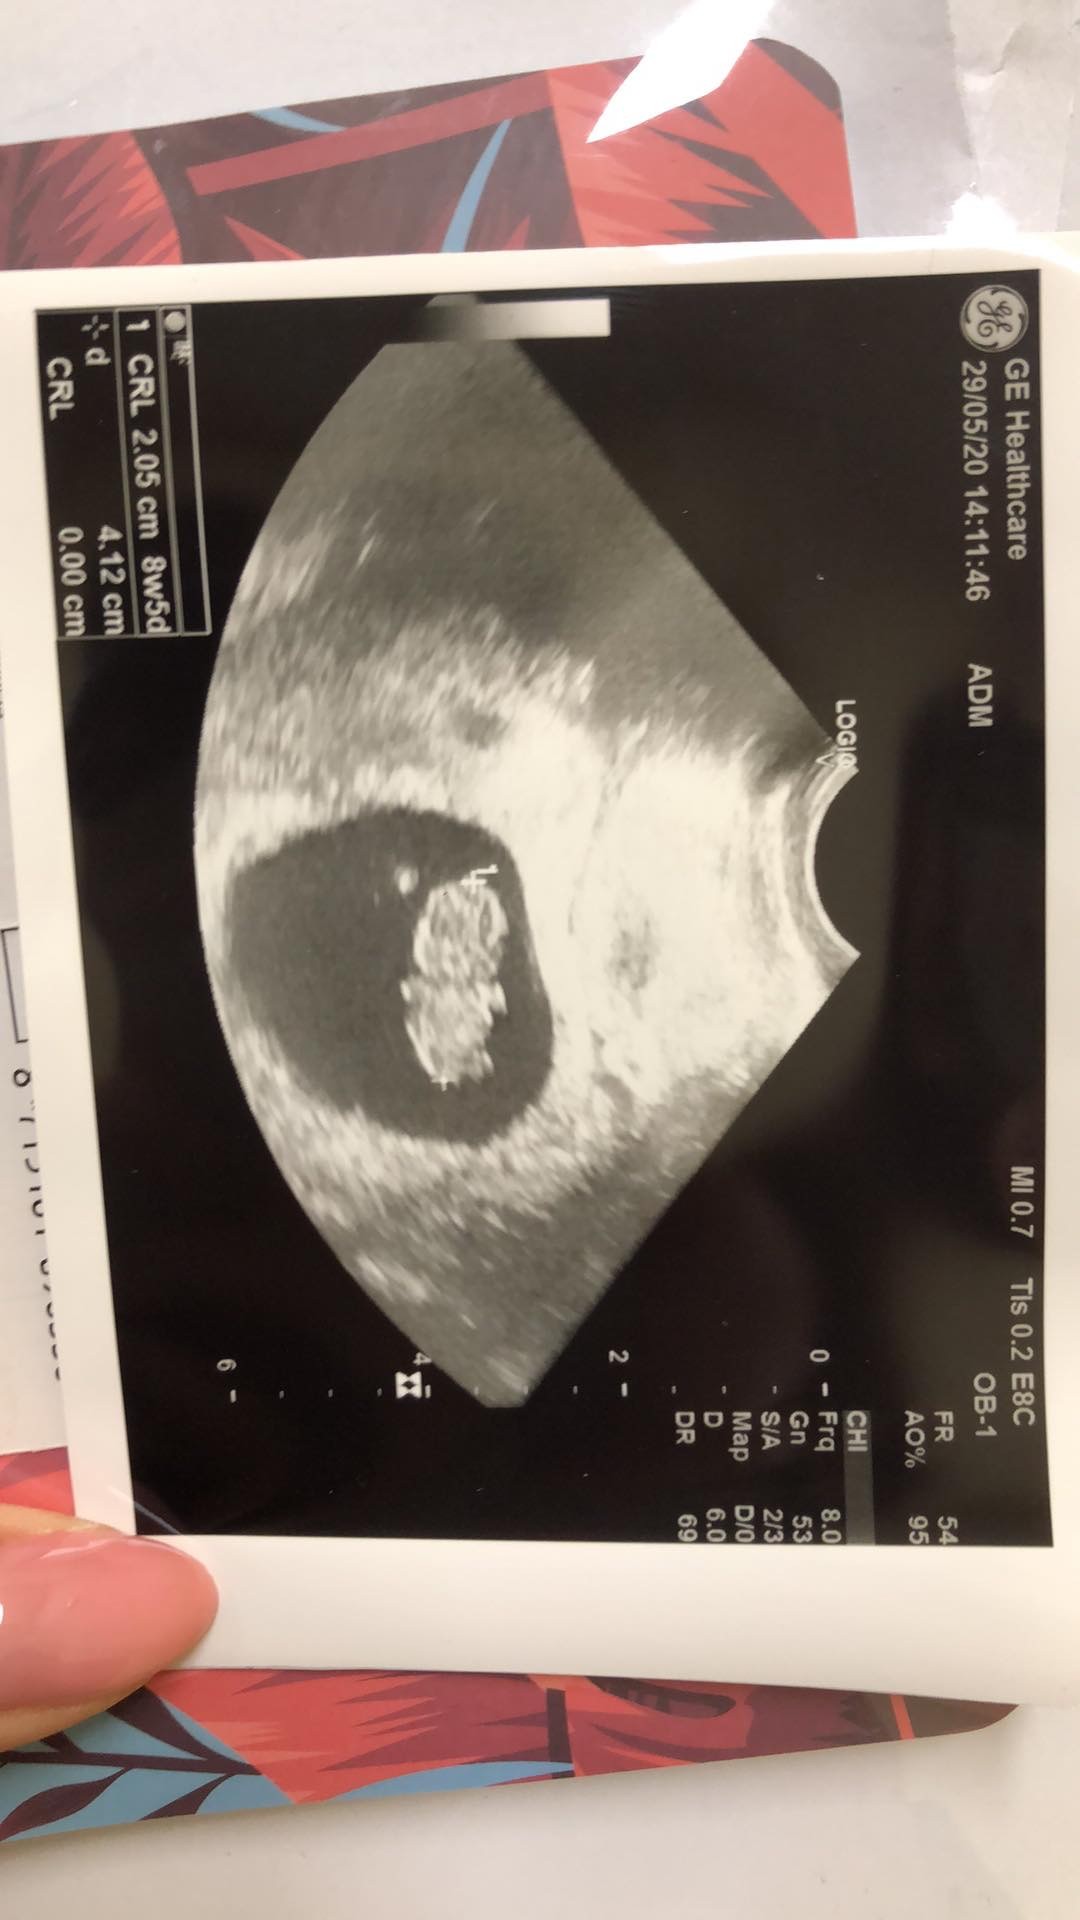

SlicznyDziewczyny mój bobas8+5